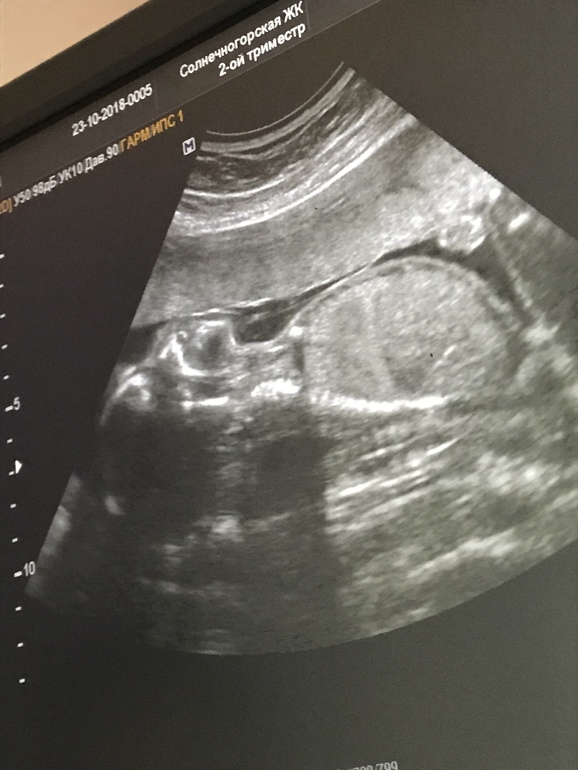

Это просто счастье)) Сегодня сходила на второе узи на сроке 20 недель и три дня. Все отлично и у нас будет мальчик!)) По совету подруги съела немного шоколадки перед процедурой и малышу это видимо пришлось по вкусу)) Он постоянно крутился, переворачивался, шевелил ручками )) Божечки))) Я так счастлива!))))

Поздравляю!! )) Смотрю вот фотки УЗИ и вроде что там везде одно и тоже, ан нет - детки все такие разные!)